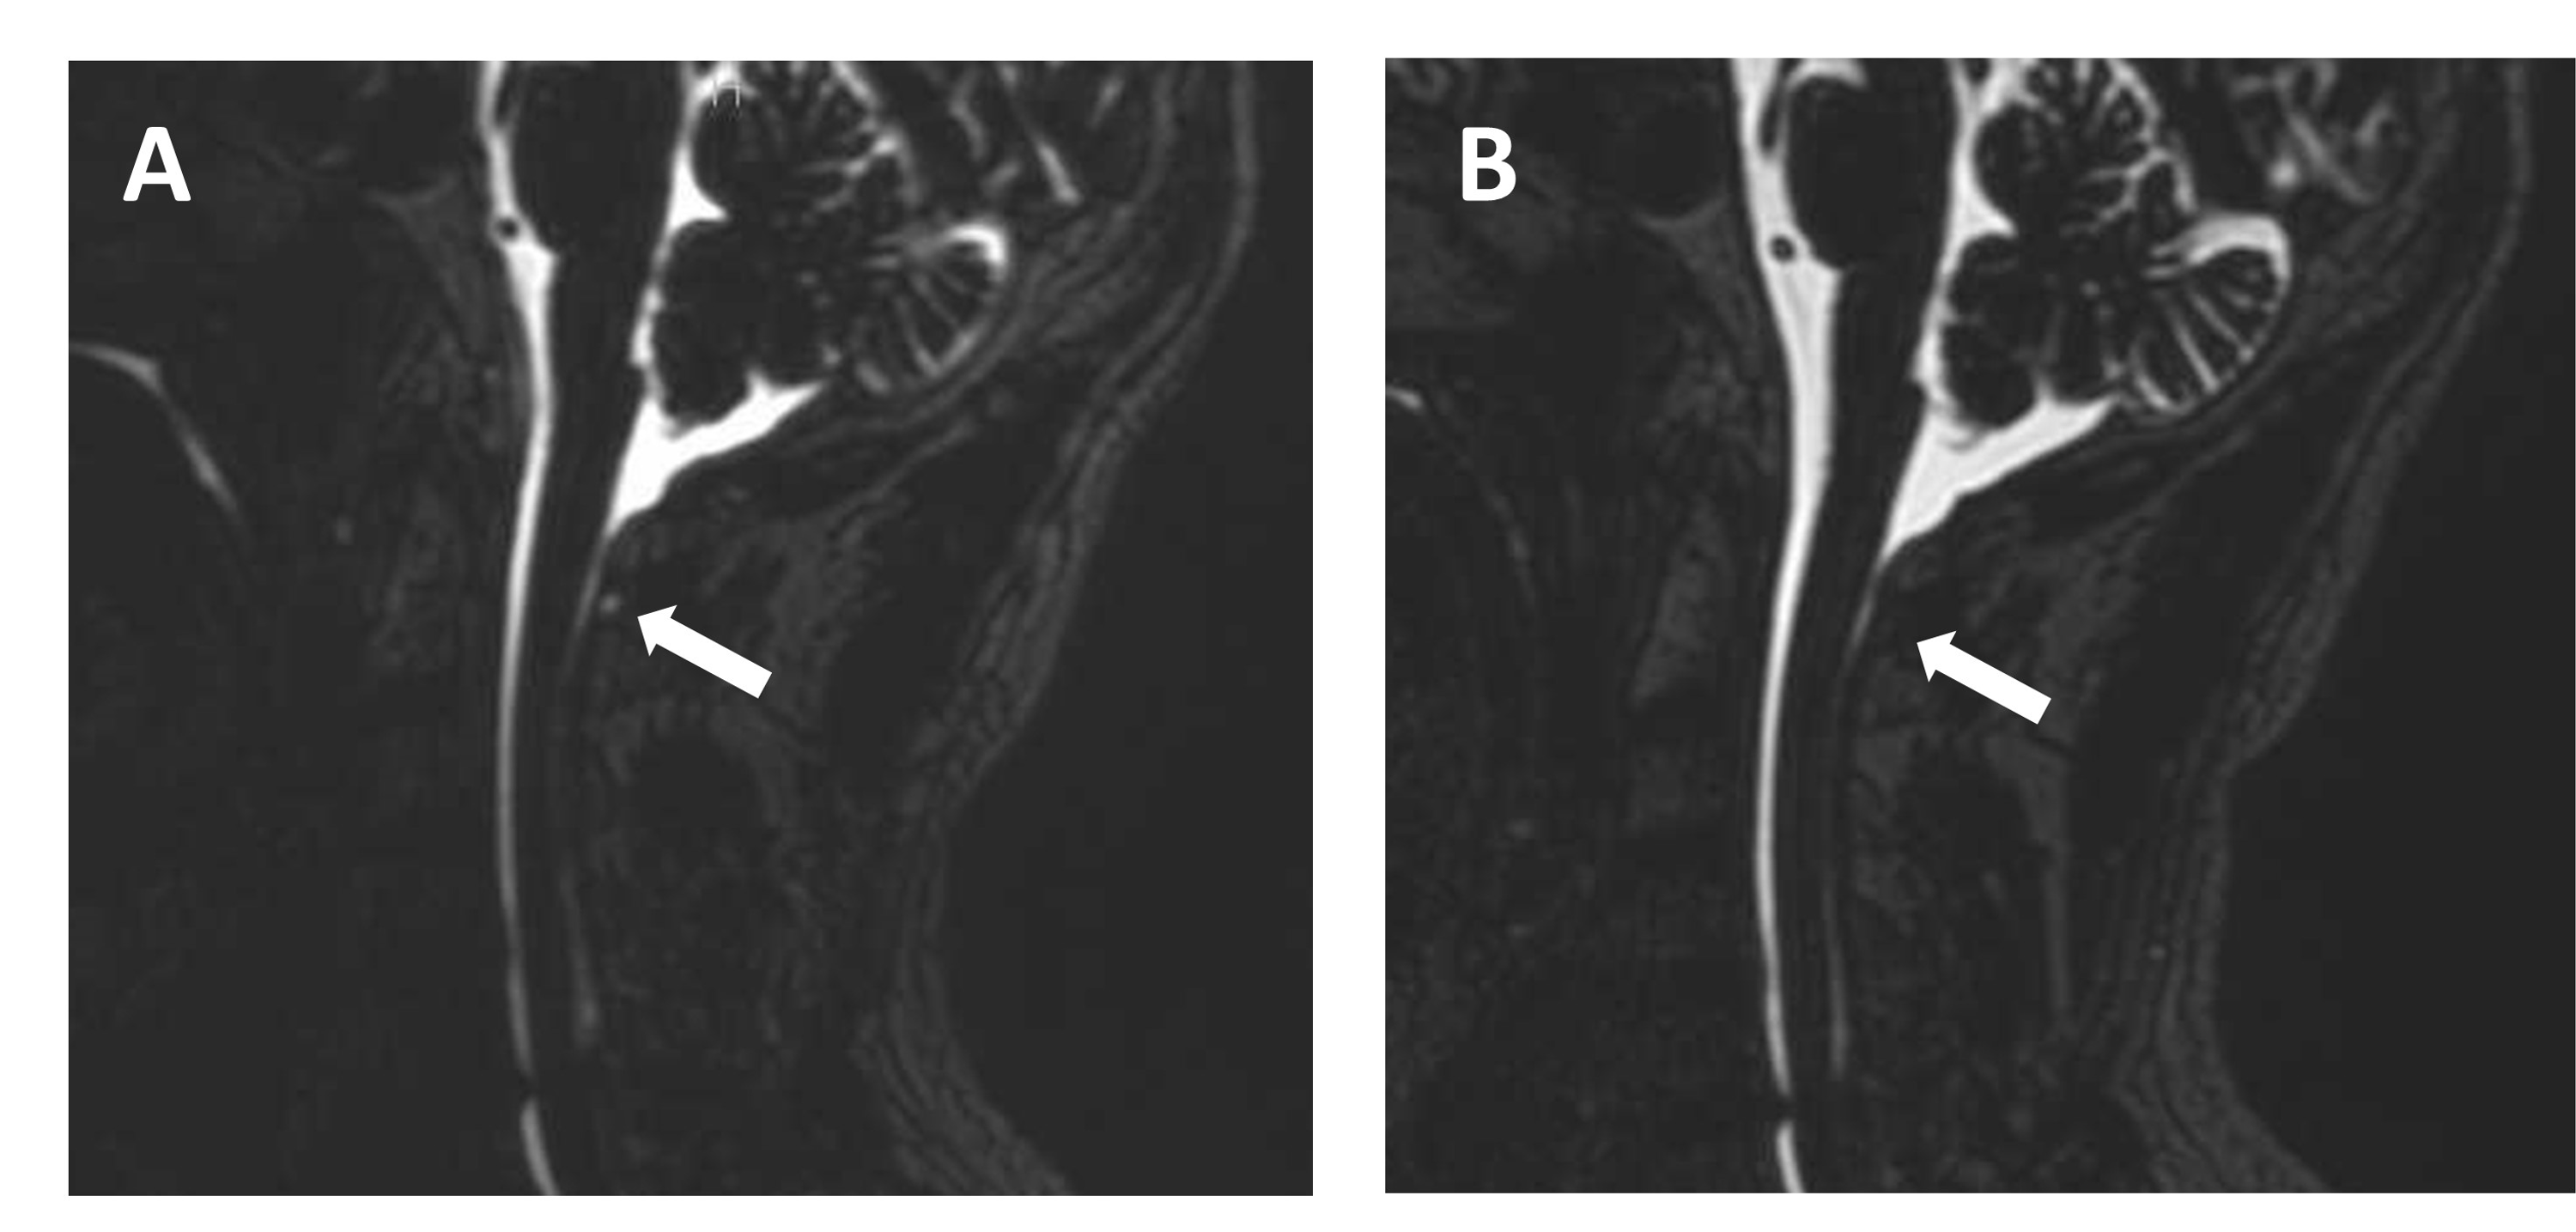

From www.semanticscholar.org

Epidural Catheter Fixation and CareA Novel Technique Semantic Scholar Catheter Epidural Blood Patch It is common after epidural or spinal. Learn about the history, anatomy, indications, and complications of epidural blood patch (ebp), a treatment for intracranial. 90 rows epidural blood patch is performed through an epidural needle. An epidural blood patch (ebp) is an injection of your blood into the epidural space near your spinal cord to stop a csf leak and. Catheter Epidural Blood Patch.

Figure 2 from Targeted epidural blood patch through a catheter in the Catheter Epidural Blood Patch An epidural blood patch (ebp) is an injection of your blood into the epidural space near your spinal cord to stop a csf leak and treat. It is common after epidural or spinal. If the blood patch is injected into epidural space through. 90 rows epidural blood patch is performed through an epidural needle. To investigate the effect of timing. Catheter Epidural Blood Patch.